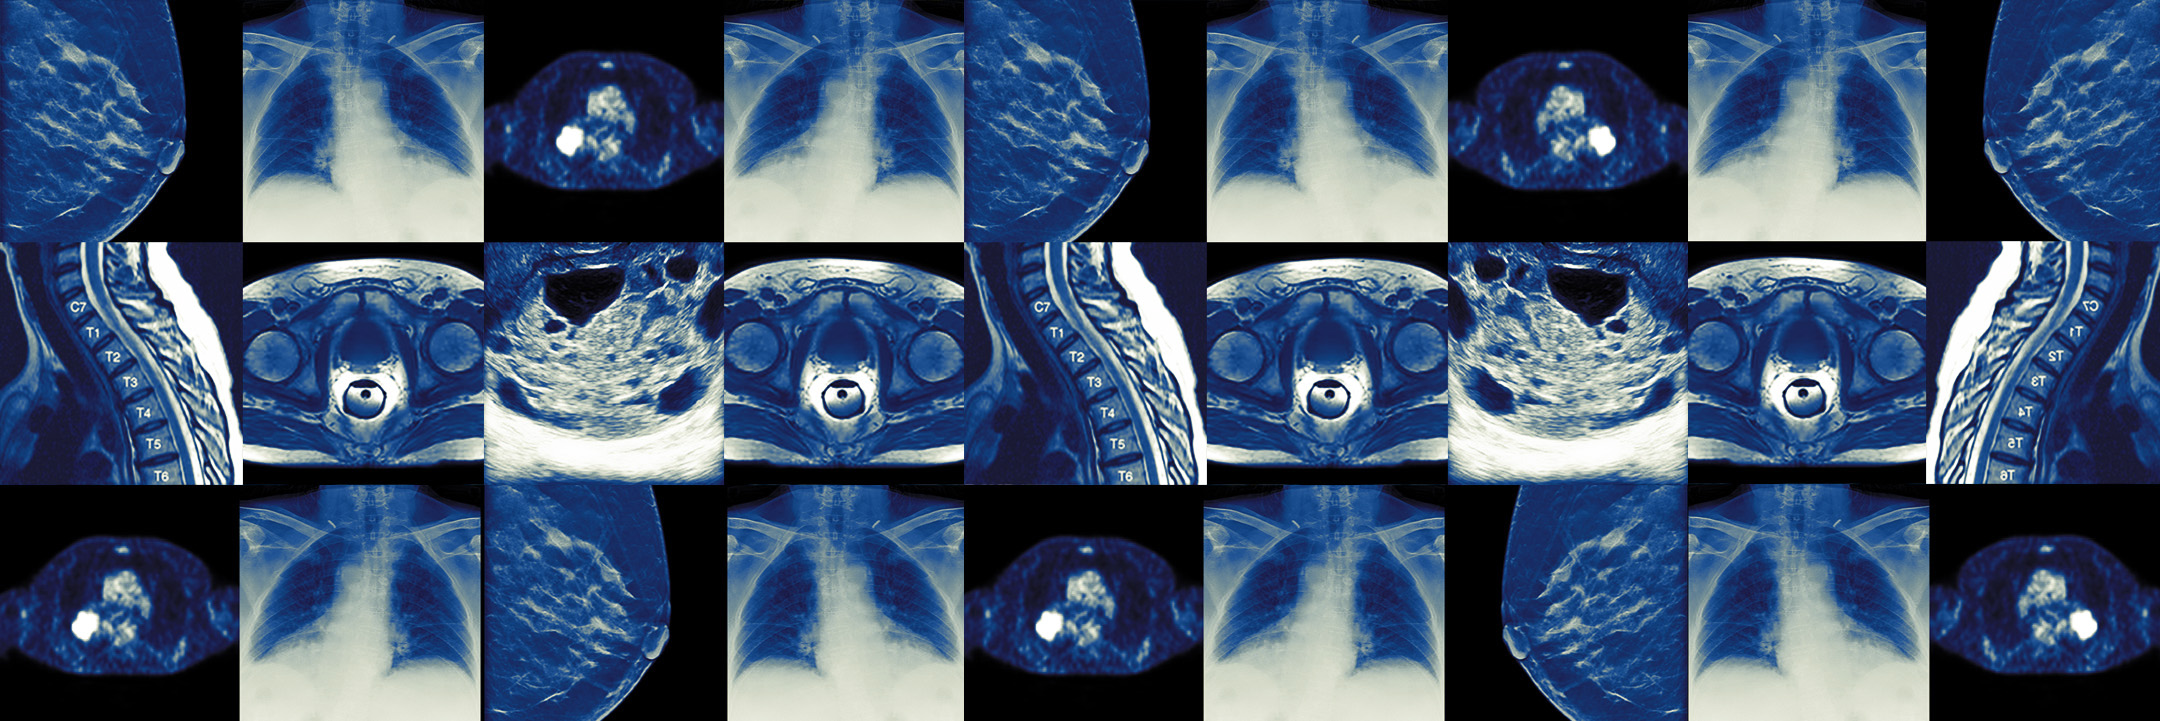

With our proprietary platforms for healthcare, we give value to real-world clinical data and images stored and updated in archives, docs, databases, machine log data, and collected from medical devices in the visible and invisible spectrum.

Trace4Research™ is a proprietary platform based on Artificial Intelligence (AI) and Data/Image Analytics for statistical analysis, automatic classification and development of AI predictive models in health at both single subject and population level.

Highly specialized algorithms based on Machine Learning, Deep Learning, Transfer Learning, Big Data Analytics and Mining, Image Processing, Image Analytics and Mining (including Radiomics) are offered as support to non-apecialized users in a user-friendly and robust way, following a very simple workflow and usability.

Trace4Research™ has been validated and used as software component to train and test several AI models embedded in our Trace4-familiy products, for a variety of clinical diseases, including neurodegenerative and cancer diseases.